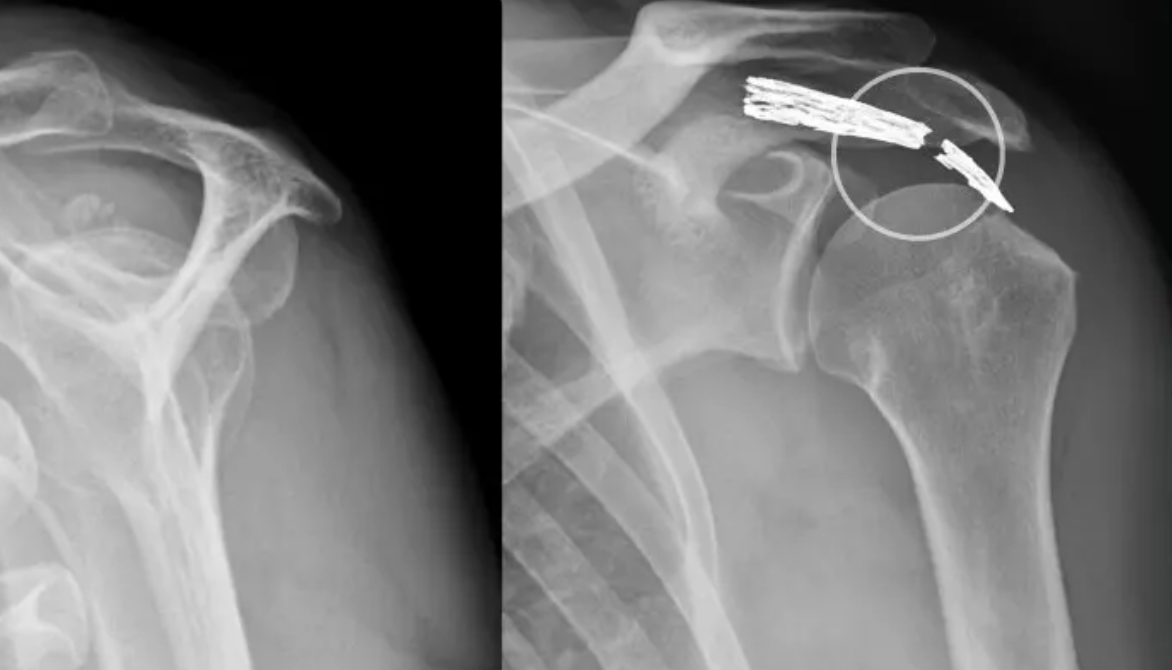

Antworten, Erfahrungen - 136 SID : deutsches-arthrose-forum - Zugang zum Deutschen Arthrose Forum Operation bei Arthrose des AC-Gelenks Im Falle einer isolierten Arthrose des AC-Gelenkes (Acromioclaviculargelenks) wird das äußere Ende des Schlüsselbeines (ca

Praxis Ole Ackermann ACGelenkSprengung. Schulterarthrose-OP - ja oder nein? Grundsätzlich gilt wie bei allen Arthroseleiden, dass mit einer konservativen Therapie eine Operation oft vermieden werden kann oder: isolierte AC-Gelenksarthrose-Operation Ist der Bandapparat des Akromioklavikulargelenks (AC-Gelenk) zwischen Schlüsselbein und Schulterdach intakt und besteht nur eine isolierte ACG-Arthrose, so wird in einem arthroskopischen Eingriff das äußere Ende des Schlüsselbeins mit einer kleinen Fräse um ca